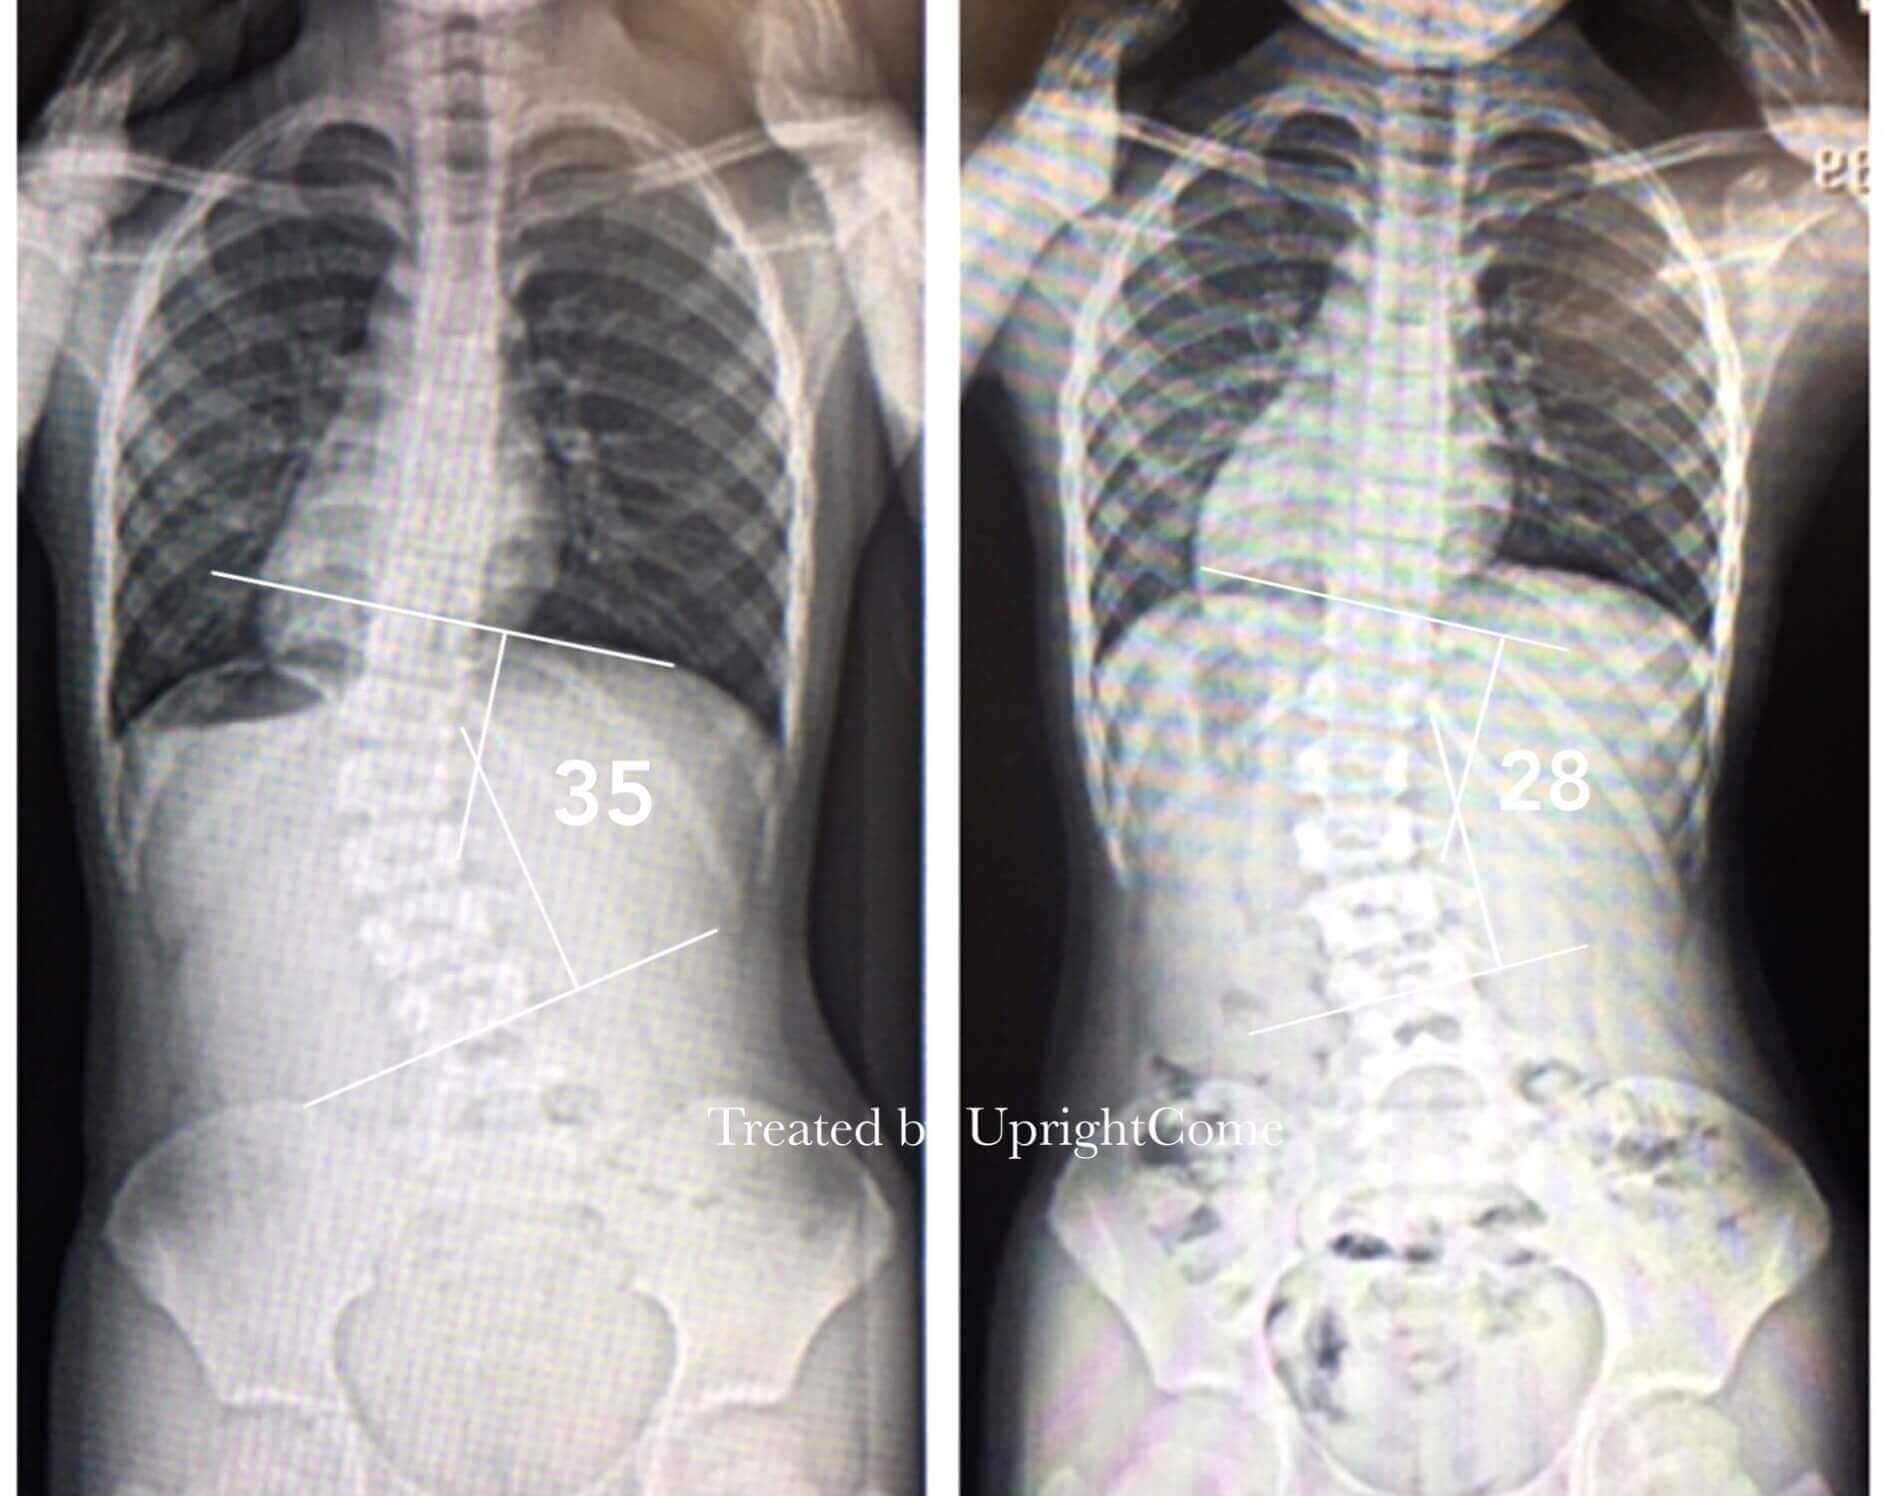

案例 26,8 歲,35 度側彎

![脊椎側彎患者經過側彎矯正治療後,腰椎側彎角度由35度減少到28度。]()